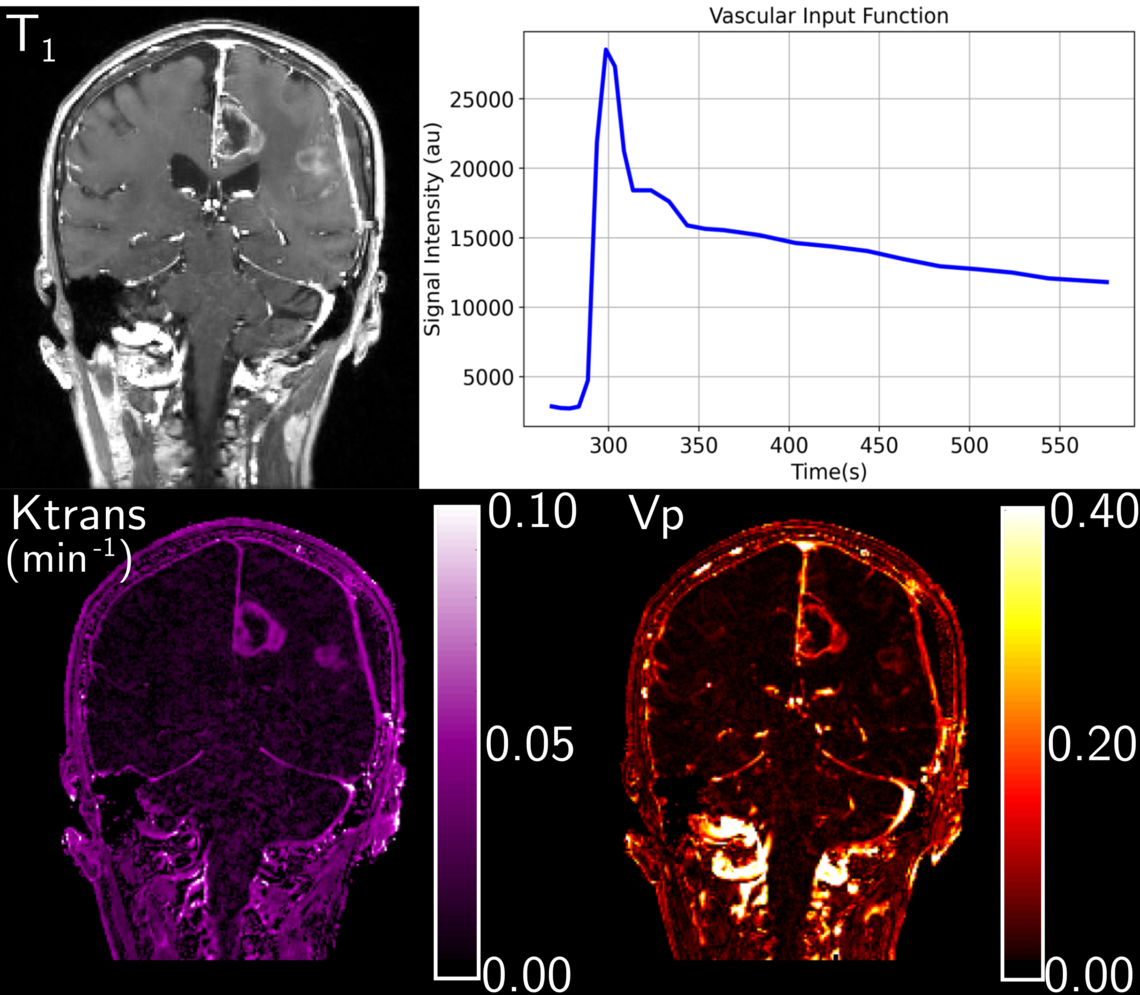

Permeability maps (K_trans and V_p) from a patient with resected GBM.

We are interested in using advanced MR imaging techniques to characterize glioblastoma multiformae.

We work on methods to help differentiate tumour from surrounding tissue. These activities are partially funded by the Canadian Cancer Society and occur in collaboration with Marc Lebel and others.